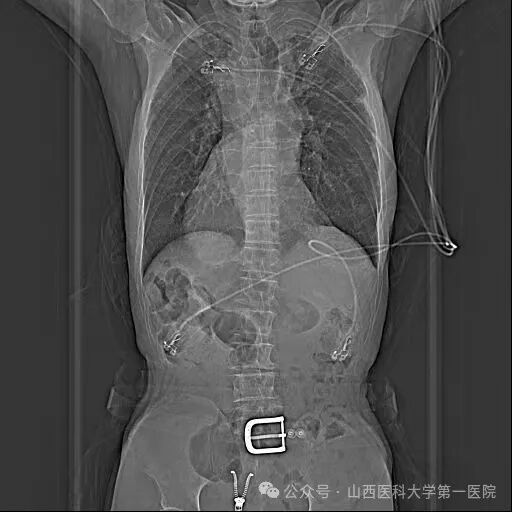

胸片示全内脏反转考虑到患者病情特殊,王睿主任医师带领团队进行了详细的术前讨论,结合患者病史、现有检查资料及技术能力、手术安全性等,与患者及家属充分沟通后,制定了手术方案:在Carto3系统下运用心腔内超声导管(ICE)及X线透视指导射频消融及左心耳封堵手术,并对手术可能出现的风险进行了汇总且制定了相应的防范措施。

左房基质及双侧环肺静脉前庭电隔离手术由王睿主任医师及电生理团队成员共同完成,整个手术过程ICE及X线透视均采用与正常患者相反(镜面)体位,穿刺左侧股静脉放置超声导管,四腔心建模,观察左心耳形态除外血栓,穿刺右股静脉,完成心室及冠状窦电极的放置,房间隔穿刺则由ICE及X线共同指导下完成,送入Pentaray电极,左房及肺静脉建模并行基质标测,左房基质可,行双侧环肺静脉前庭电隔离,观察30分钟,双侧肺静脉线性阻滞,反复刺激未诱发心动过速。撤出消融导管,沿长鞘将猪尾导管送入左心耳,左心耳到位困难,考虑穿刺位点偏后偏上,再次行房间隔穿刺,由于房间隔膨出瘤导致穿刺鞘贴靠困难,换用可调弯针鞘,腔内超声指导下再次行房间隔穿刺术,将导丝送至左上肺静脉,换用左心耳封堵导引鞘,送入猪尾导管,左心耳造影并测量,透视下释放封堵器,腔内超声示封堵良好。患者术后安返病房,无并发症发生,平卧12小时后下床恢复正常活动,目前已顺利出院。